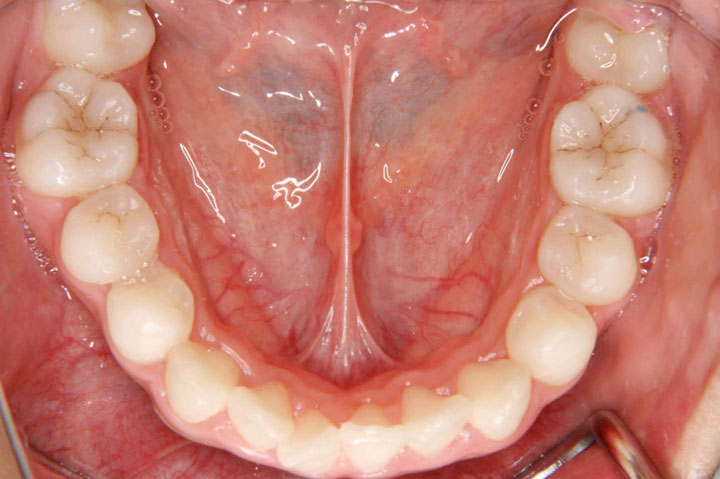

叢生(乱ぐい歯)

上顎前突(出っ歯)

上下の歯のデコボコを気にされて来院された小学生の女子です。まず前期治療としてヘッドギアーによる上顎大臼歯の遠心移動とクォードヘリックス、バイヘリックスによる上下顎の拡大を行いました。その後、永久歯への交換を待ってエッジワイズ装置(デーモンシステム)による配列を行っております。